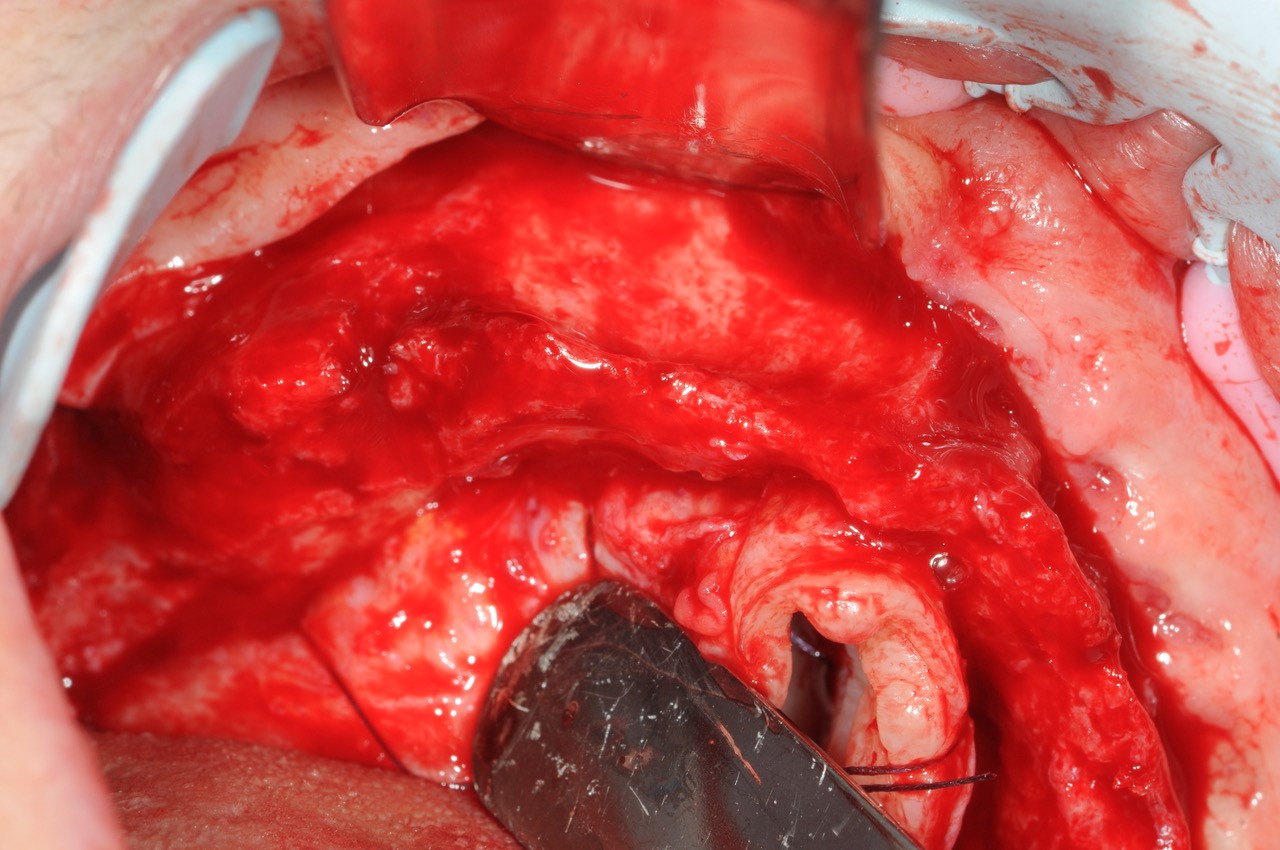

18/21 - 6 months post-op: situation at re-entry shows stable bone

Reconstruction of maxillary ridge with maxgraft® block - Amit Patel